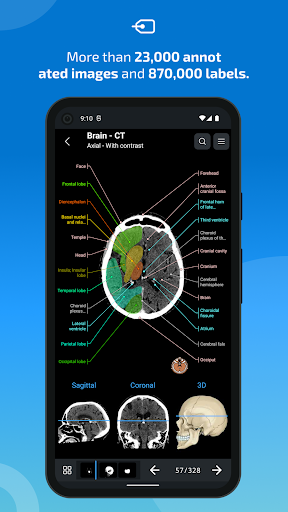

- عرض التشريحية يعرض الآن المزيد من التسميات

- يمكنك الآن إخفاء الهياكل واحداً تلو الآخر (زر جديد داخل نافذة الوصف المنبثقة) وعرضها مرة أخرى في القائمة الصحيحة